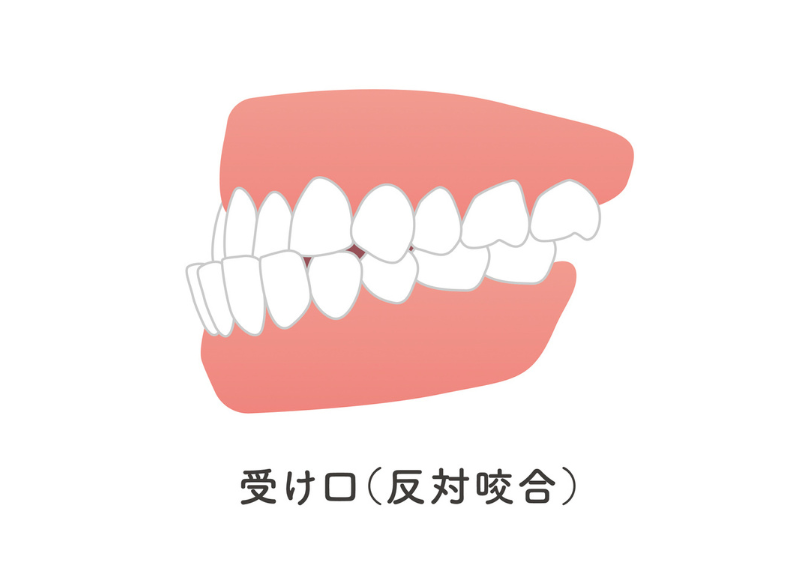

1. 受け口(反対咬合)

下の前歯が上の前歯より前に出ている状態です。

受け口は骨格的な成長が関与するため、できるだけ早期(3歳〜6歳頃)の対応が望ましいとされています。

放置すると下顎が過剰に成長し、将来的に外科手術が必要になるリスクが高まるため、早めの受診をお勧めします。プレオルソ(ムーシールドタイプ)などで早期に改善を図ります。